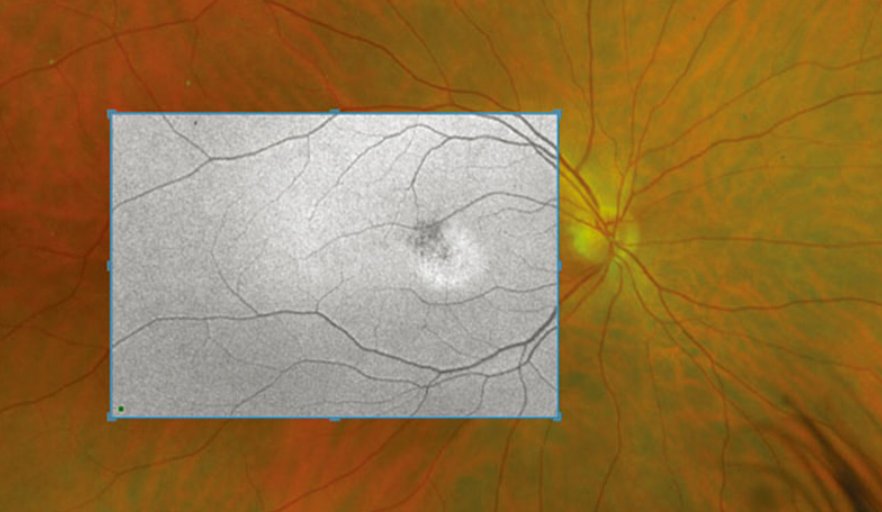

広角眼底カメラ

網膜の広範囲を一度に撮影可能。糖尿病網膜症や網膜剥離の早期発見に威力を発揮します。